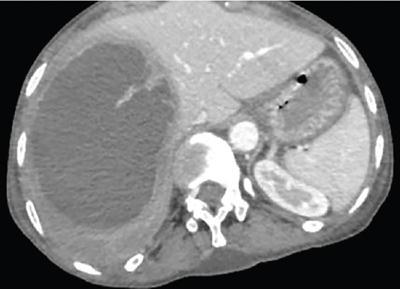

Shrinivas B. Desai, Ritu K. Kashikar, Shreya Shukla Radiological signs are classical and distinctive abnormalities characteristic of a disease. These can be seen on any imaging modality. Resemblance to commonly seen objects and patterns form the basis of radiological signs. The aim is to help the reader associate, understand and memorize these pathologies with the aid of signs. Various signs pertinent to hepatobiliary system are described in the chapter. Described on MRI when liver lesion shows a peripheral rim of high T2 signal intensity with the centre of the lesion appearing isointense to the background of noncirrhotic liver on T2WI mimicking an atoll. It is considered a characteristic sign of an inflammatory hepatic adenoma (image) but is only seen in about one-third of cases Extrinsic smooth impression over medial aspect of duodenum along its posteroinferior aspect, seen in pancreatic head pathologies like carcinoma. This sign is seen in pancreatic adenocarcinoma Presence of a persistently hyperattenuating dot within a lesion on arterial and portal venous CT. This corresponds with peripheral nodular enhancement seen on dynamic MR. Presence of bright dot suggests that the lesion is a hemangioma and helps in ruling out metastasis Ultrasound appearance of multiple cystic spaces or lesions that has been used to describe the appearance of an intraductal papillary mucinous neoplasm of the pancreas. Seen on contrast CT in portal hypertension. The appearance is based on resemblance to Medusa from Greek mythology. Dilated engorged paraumbilical veins radiating across umbilicus to join systemic veins is seen. This sign is seen in Caroli’s disease on contrast CT. Enhancing dots within dilated intrahepatic bile ducts represent portal radicles. Caroli’s disease Irregularly dilated pancreatic duct with multiple strictures and intervening dilatation with associated dilated side ductules resemble multiple lakes supplied by a single territory. Best seen in MRCP images. Chronic pancreatitis It is a finding on MRI and CT and is best seen on MRI T2-weighted and postcontrast T1-weighted sequences. Small necrotic/purulent areas in the pyogenic abscess ‘cluster’ together and then coalesce into a larger necrotic/purulent areas, eventually becoming a larger septated abscess cavity. At the periphery of these clusters: Associated with pyogenic hepatic abscesses and can help differentiate pyogenic abscesses from other types of liver lesions Abrupt termination of gas within the proximal colon at the level of radiological splenic flexure. The inflammatory exudates in pancreatitis extend to the phrenicocolic ligament giving rise to this sign Seen on grey scale ultrasound as a reverberation artifact when small calcific or highly reflective objects are imaged. The colour comet-tail artifact is an ultrasonographic sign seen in a number of situations when colour Doppler scanning is performed. This sign occurs in cases of traumatic right-sided diaphragmatic rupture with resultant partial herniation of liver through the defect. Separation of the herniated liver from its intra-abdominal component is via a small constriction at the level of diaphragm resembling a cottage loaf. Cottage loaf is a particular shape of bread in which larger and smaller roughly spherical balls are squashed together. Traumatic right-sided diaphragmatic rupture with resultant partial herniation of liver Bile eccentrically outlines luminal stone, creating a low attenuation crescent. Best seen on MRCP images. Choledocholithiasis Dilatation of both pancreatic duct and CBD is referred to as the double duct sign. Positive double duct sign suggests the diagnosis of carcinoma of the head of the pancreas and ampullary tumours and is hence considered ominous. Occasionally the sign may be seen in impacted gallstone in the distal duct. This feature is seen in patients with liver abscess on contrast-enhanced CT. A double, inner hyperattenuating and outer hypoattenuating rim is seen surrounding the hypodense abscess. The inner hyperattenuating rim corresponds to the enhancing abscess membrane, while the outer rim corresponds to the edema of the surrounding liver which appears hypodense and may show delayed enhancement. Liver abscess A positive duct penetrating sign is when a mass is penetrated by an unobstructed pancreatic duct; this makes focal pancreatitis the most likely cause rather than pancreatic carcinoma. This sign is best appreciated on MRCP (or ERCP). A radiographic sign that can be useful in differentiating between focal pancreatitis (inflammatory pancreatic mass) from pancreatic carcinoma. The duct-penetrating sign on MRCP is more helpful in differentiating between these two entities than a delayed enhancement pattern on CT or MRI It occurs when there is both limy bile and a gallstone in the common bile duct. The linear vertical radiopaque bile forms the line of the exclamation mark (i.e. !), whilst a more distal calculus forms the ‘dot’ at the end of the exclamation mark. Pathognomonic imaging sign of the rare diagnosis of limy bile on plain abdominal radiography Nonenhancing ruptured lesion with peripheral rim enhancement showing discontinuity from the rest of the liver and protruding from the liver surface is called the enucleation sign. Ruptured HCC Enlargement of the pericholecystic space. One of the signs of liver cirrhosis Can be seen on technetium 99m sulphur colloid scans of the liver and spleen, as well as CT studies. It occurs as a focal area of increased radiopharmaceutical uptake in the medial segment of the left hepatic lobe (segment IV) occurring as a result of SVC obstruction and portosystemic venous shunting between the superior vena cava and the left portal vein via the internal thoracic and paraumbilical veins. The equivalent of this sign may also be seen on contrast-enhanced CT scans as a hypervascular region. Budd–Chiari syndrome causes the hot spot sign in the caudate lobe

16) The double target sign